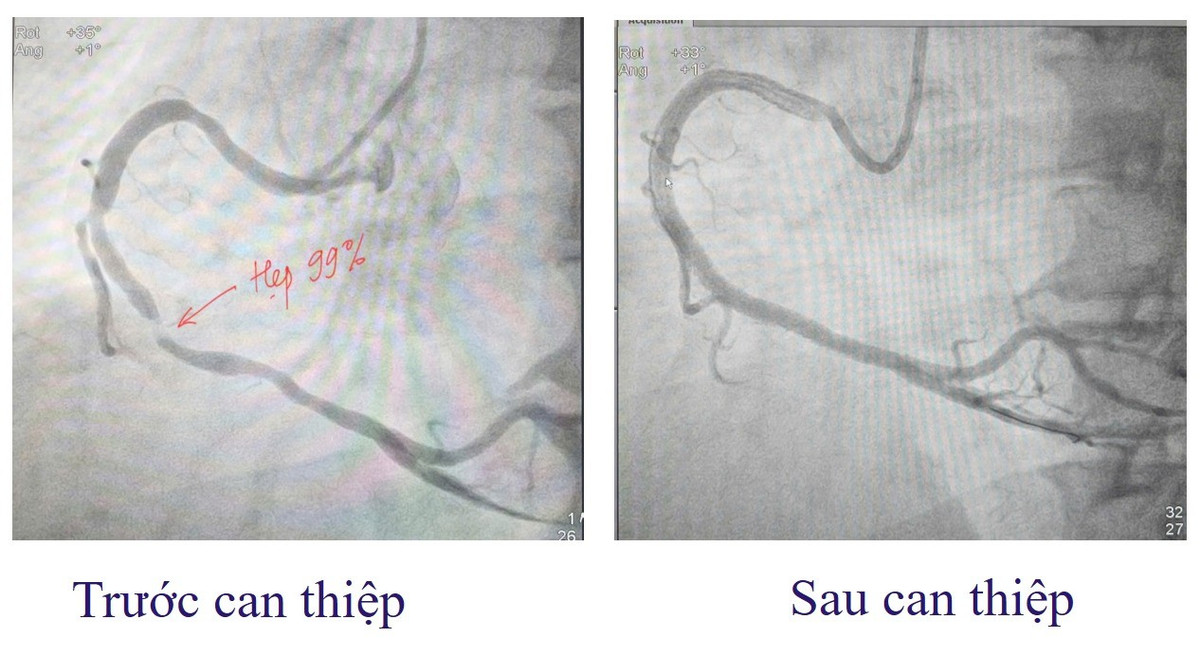

Ngay lập tức, bệnh nhân được cấp cứu theo phác đồ hội chứng vành cấp và chỉ định chụp động mạch vành qua da cấp cứu. Kết quả cho thấy: Động mạch vành phải (RCA) đoạn 2-3 hẹp tới 99%. RCA đoạn 1 hẹp 60%. Đây là tình trạng tắc hẹp mạch vành nguy kịch, có thể dẫn đến hoại tử cơ tim lan rộng và đe dọa tính mạng nếu không được can thiệp tái thông mạch máu kịp thời.

Kíp can thiệp do ThS.BS Đinh Danh Trình, Trưởng khoa Tim mạch, cùng ê kíp đã nhanh chóng tiến hành can thiệp đặt stent mạch vành, tái thông đoạn mạch bị hẹp. Ca can thiệp diễn ra thành công, giúp khôi phục dòng máu nuôi cơ tim, ngăn chặn nguy cơ nhồi máu lan rộng và biến chứng nguy hiểm.